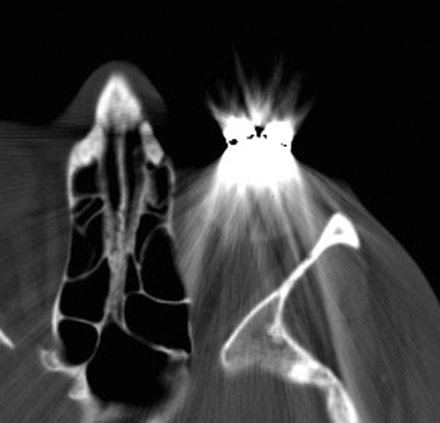

Implantation of gold and platinum eyelid weights into the upper eyelid is a static reanimation procedure for treating lagophthalmos.2 Although gold weights are more commonly used, platinum weights have a thinner profile and therefore offer an increased aesthetic benefit.3 Available eyelid implant designs include curved metal sheets with holes to permit anchoring with a suture (Fig 3) and flexible metal chains. In-growth of fibrous tissue through the holes also helps secure the weight in position. Eyelid weights are secured to the superficial aspect of the upper eyelid tarsal plate. The eyelid weights generally produce considerable streak artifacts on CT, which can obscure surrounding structures (Fig 4). Platinum and gold eyelid weights are considered MR imaging–compatible up to 7T4,5 but may cause local field inhomogeneity (Fig 5). Complications related to eyelid weight implantation include suboptimal eyelid contour, infection, allergic reaction, migration, and extrusion.6

Eyelid weight. Axial CT image shows extensive streak artifacts related to the left eyelid weight, which obscures surrounding structures.